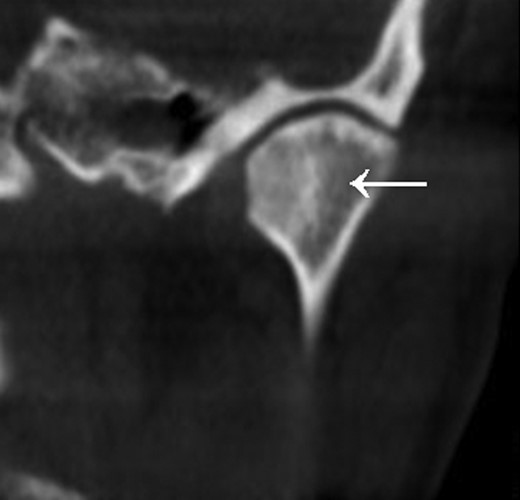

A full-body skeletal scintigraphy was done, which did not show an obvious pathology in the right TMJ (Fig. 3). Due to this, a SPECT/CT was performed for clarification. High uptake of nuclides was seen around the osteolysis of the right condyle (Fig. 4). Sclerotic changes without increased uptake were noted in the left condyle (Fig. 5).

The sclerosis of the left TMJ was suspected to be a non-active metastasis.

In summary, from the radiological findings bilateral TMJ metastases were diagnosed, which were, however, not confirmed histologically.